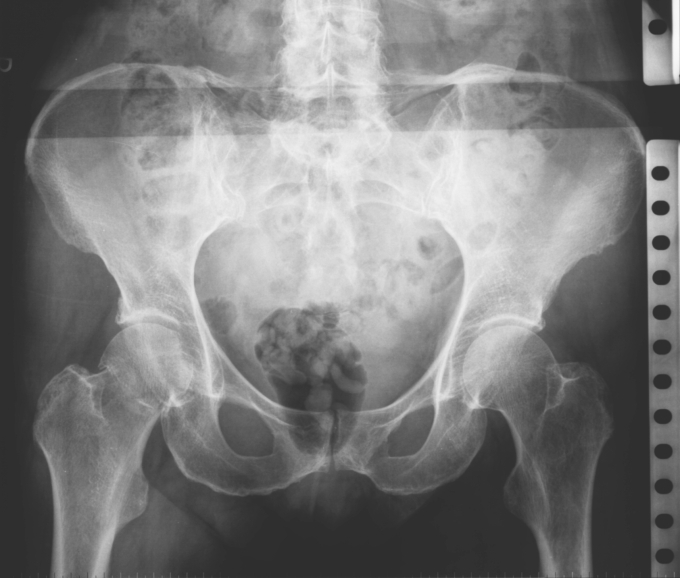

Series: 09012001

2. Series: 09012001

63 jaehrige Frau nach Sturz auf die rechte Huefte. Fraktur?